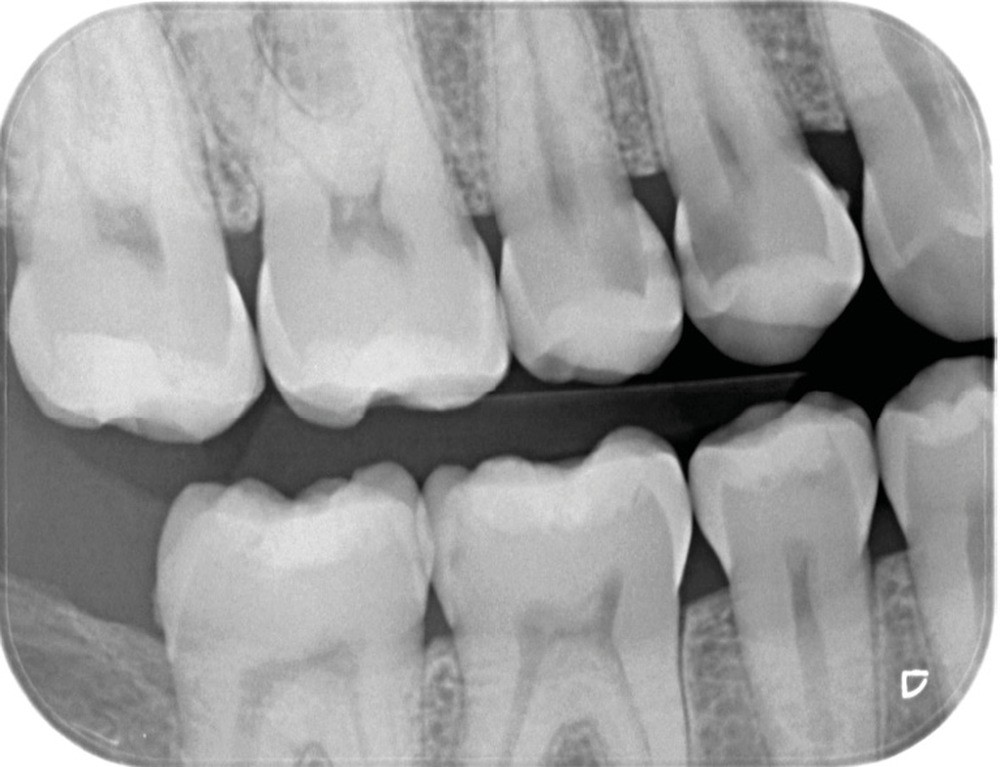

FAUX. Le diagnostic précoce des lésions carieuses se base sur un diagnostic clinique visuel précis à l’aide des classifications visuelles internationales (ICDAS ou ICCMS) et de l’utilisation d’aides optiques (loupes, microscope, caméra avec signal fluorescent ou non) et sur un diagnostic radiographique (à l’aide de deux bitewing, l’un à droite l’autre à gauche) (fig. 1).